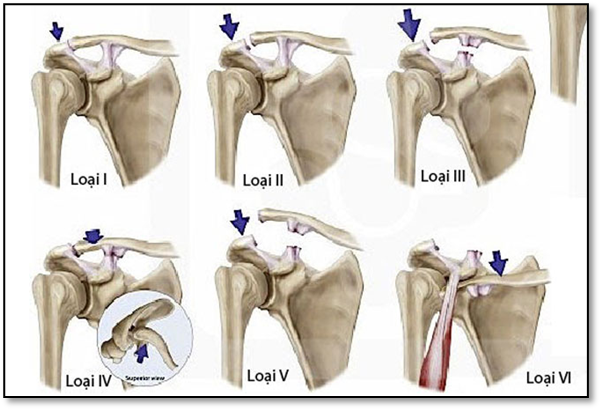

Tùy theo độ lệch và tổn thương dây chằng, sai khớp cùng đòn được phân thành 6 cấp độ (theo tác giả Rockwood):

• Độ I: giãn dây chằng cùng đòn

• Độ II: đứt dây chằng cùng đòn, giãn dây chằng quạ đòn

• Độ III: đứt dây chằng quạ đòn, khớp cùng đòn trật hoàn toàn

• Độ IV: đầu ngoài xương đòn trật ra sau, vào hoặc xuyên qua cơ thang

• Độ V:  đầu ngoài xương đòn di lệch lên trên rất nhiều

• Độ VI: với phần xương đòn đi lệch xuống dưới mỏm cùng vai hoặc mỏm quạ. Khoảng gian quạ – đòn thu hẹp so với bên lành.

Hình ảnh: Phân loại trật khớp cùng đòn theo Rockwood